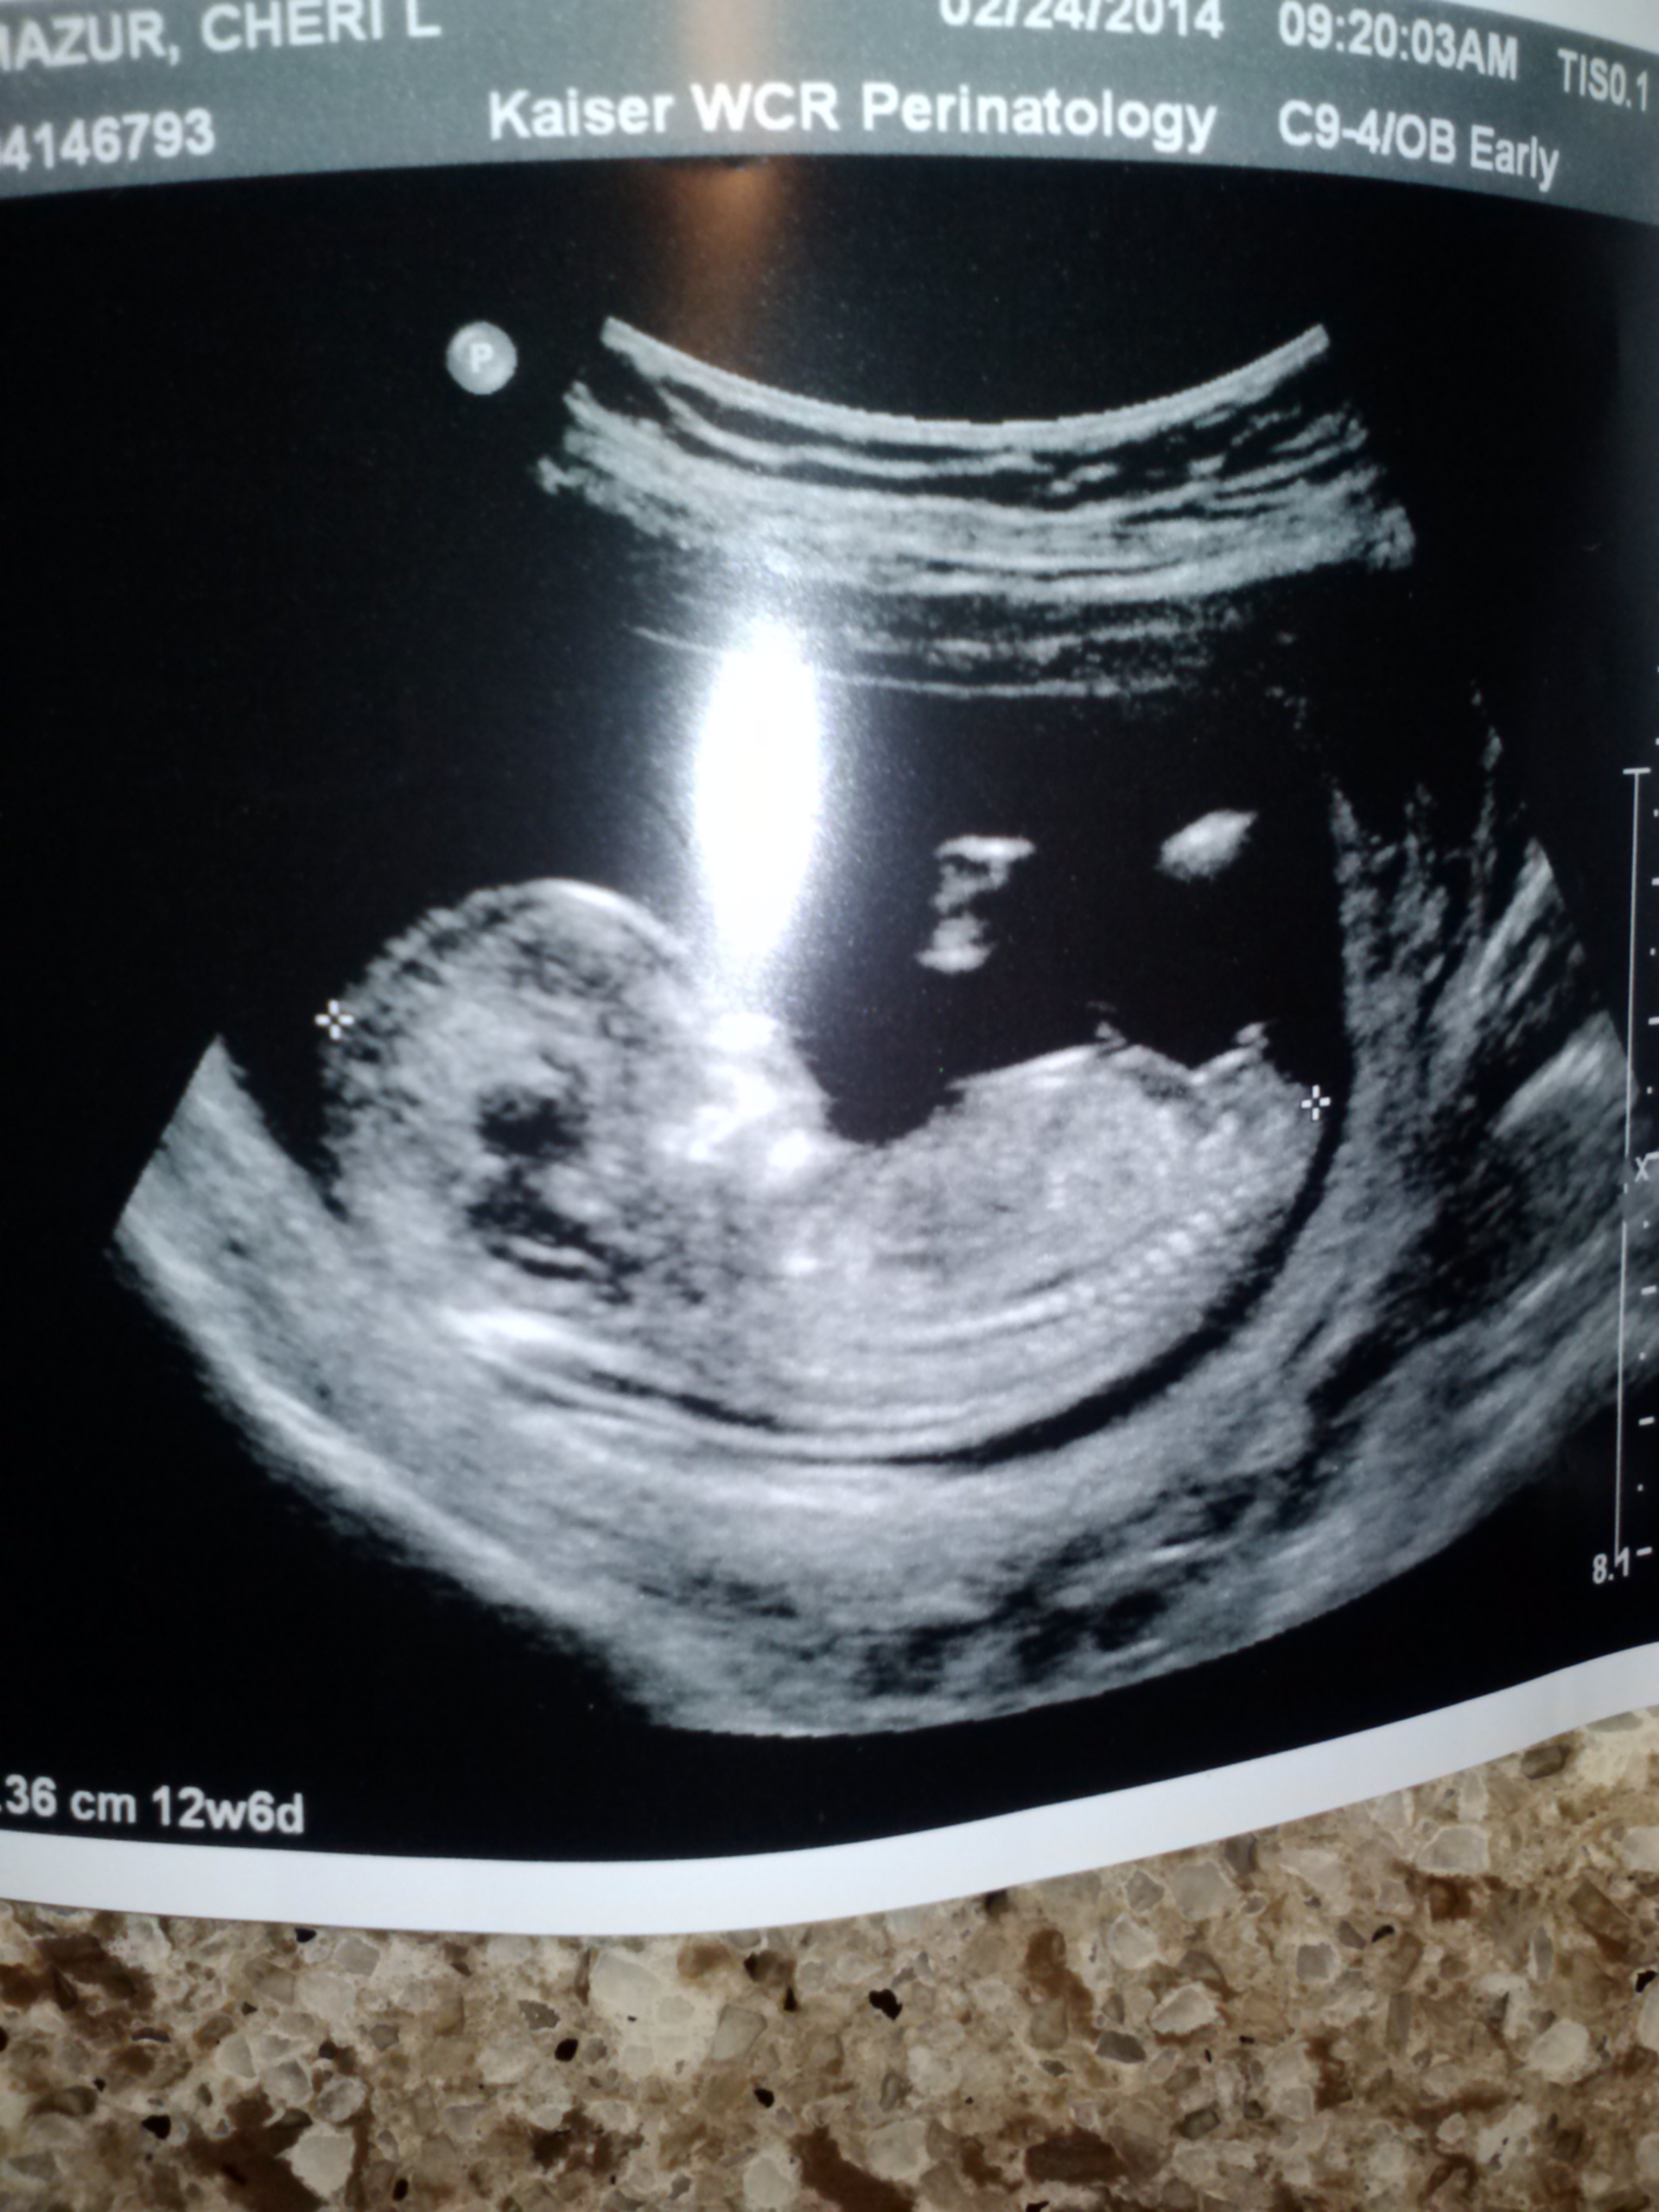

Attachment 17688

Looks girly but potty shots aren't reliable at this stage from what I understand. Do you have a nub shot?